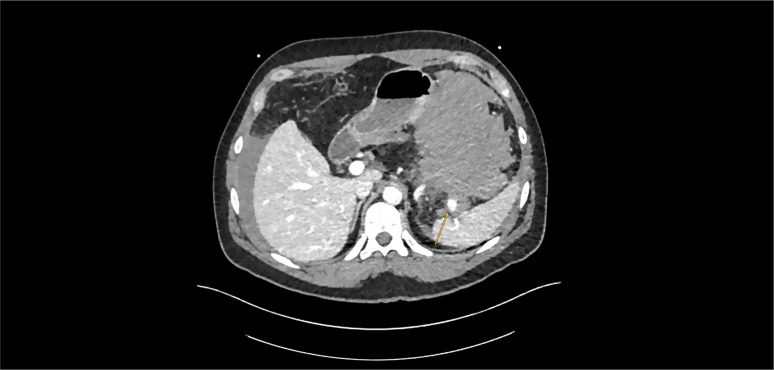

摘要脾动脉瘤是一种罕见但可能危及生命的疾病。SAA可发生在急性或慢性胰腺炎假性动脉瘤、医源性(胰腺/脾手术后)或创伤后。如果有症状,需要紧急治疗,因为它有很高的破裂风险。病例表现:这是一个动脉瘤破裂的病例,以一种不寻常的方式表现出来:首先是急性腹部,其次是迟发性失血性休克。只有紧急剖腹手术和脾切除术才挽救了病人的生命。结论:如果在CT扫描上发现脾动脉假性动脉瘤,无论其大小和患者如何,破裂的风险都增加,应积极处理。伴随的腹部发现和疾病可能延误诊断和低估风险。

Introduction: Splenic artery aneurysm (SAA) is a rare but potentially life-threatening condition. SAA can occur following an acute or chronic pancreatitis as a pseudoaneurysm, iatrogenic (post-pancreatic/splenic surgery) or post-traumatic. If symptomatic, it needs to be treated urgently as it has a high risk of rupture.

Case presentation: Here is a case where a ruptured aneurysm presented in an unusual manner: first as an acute abdomen and second, delayed, as hemorrhagic shock. Only emergency laparotomy and splenectomy saved the patient's life.

Conclusion: If a splenic artery pseudoaneurysm is detected on CT scan, there is an increased risk of rupture irrespective of the size and the patient that should be proactively managed. Concomitant abdominal findings and diseases can delay diagnosis and underestimate the risk.